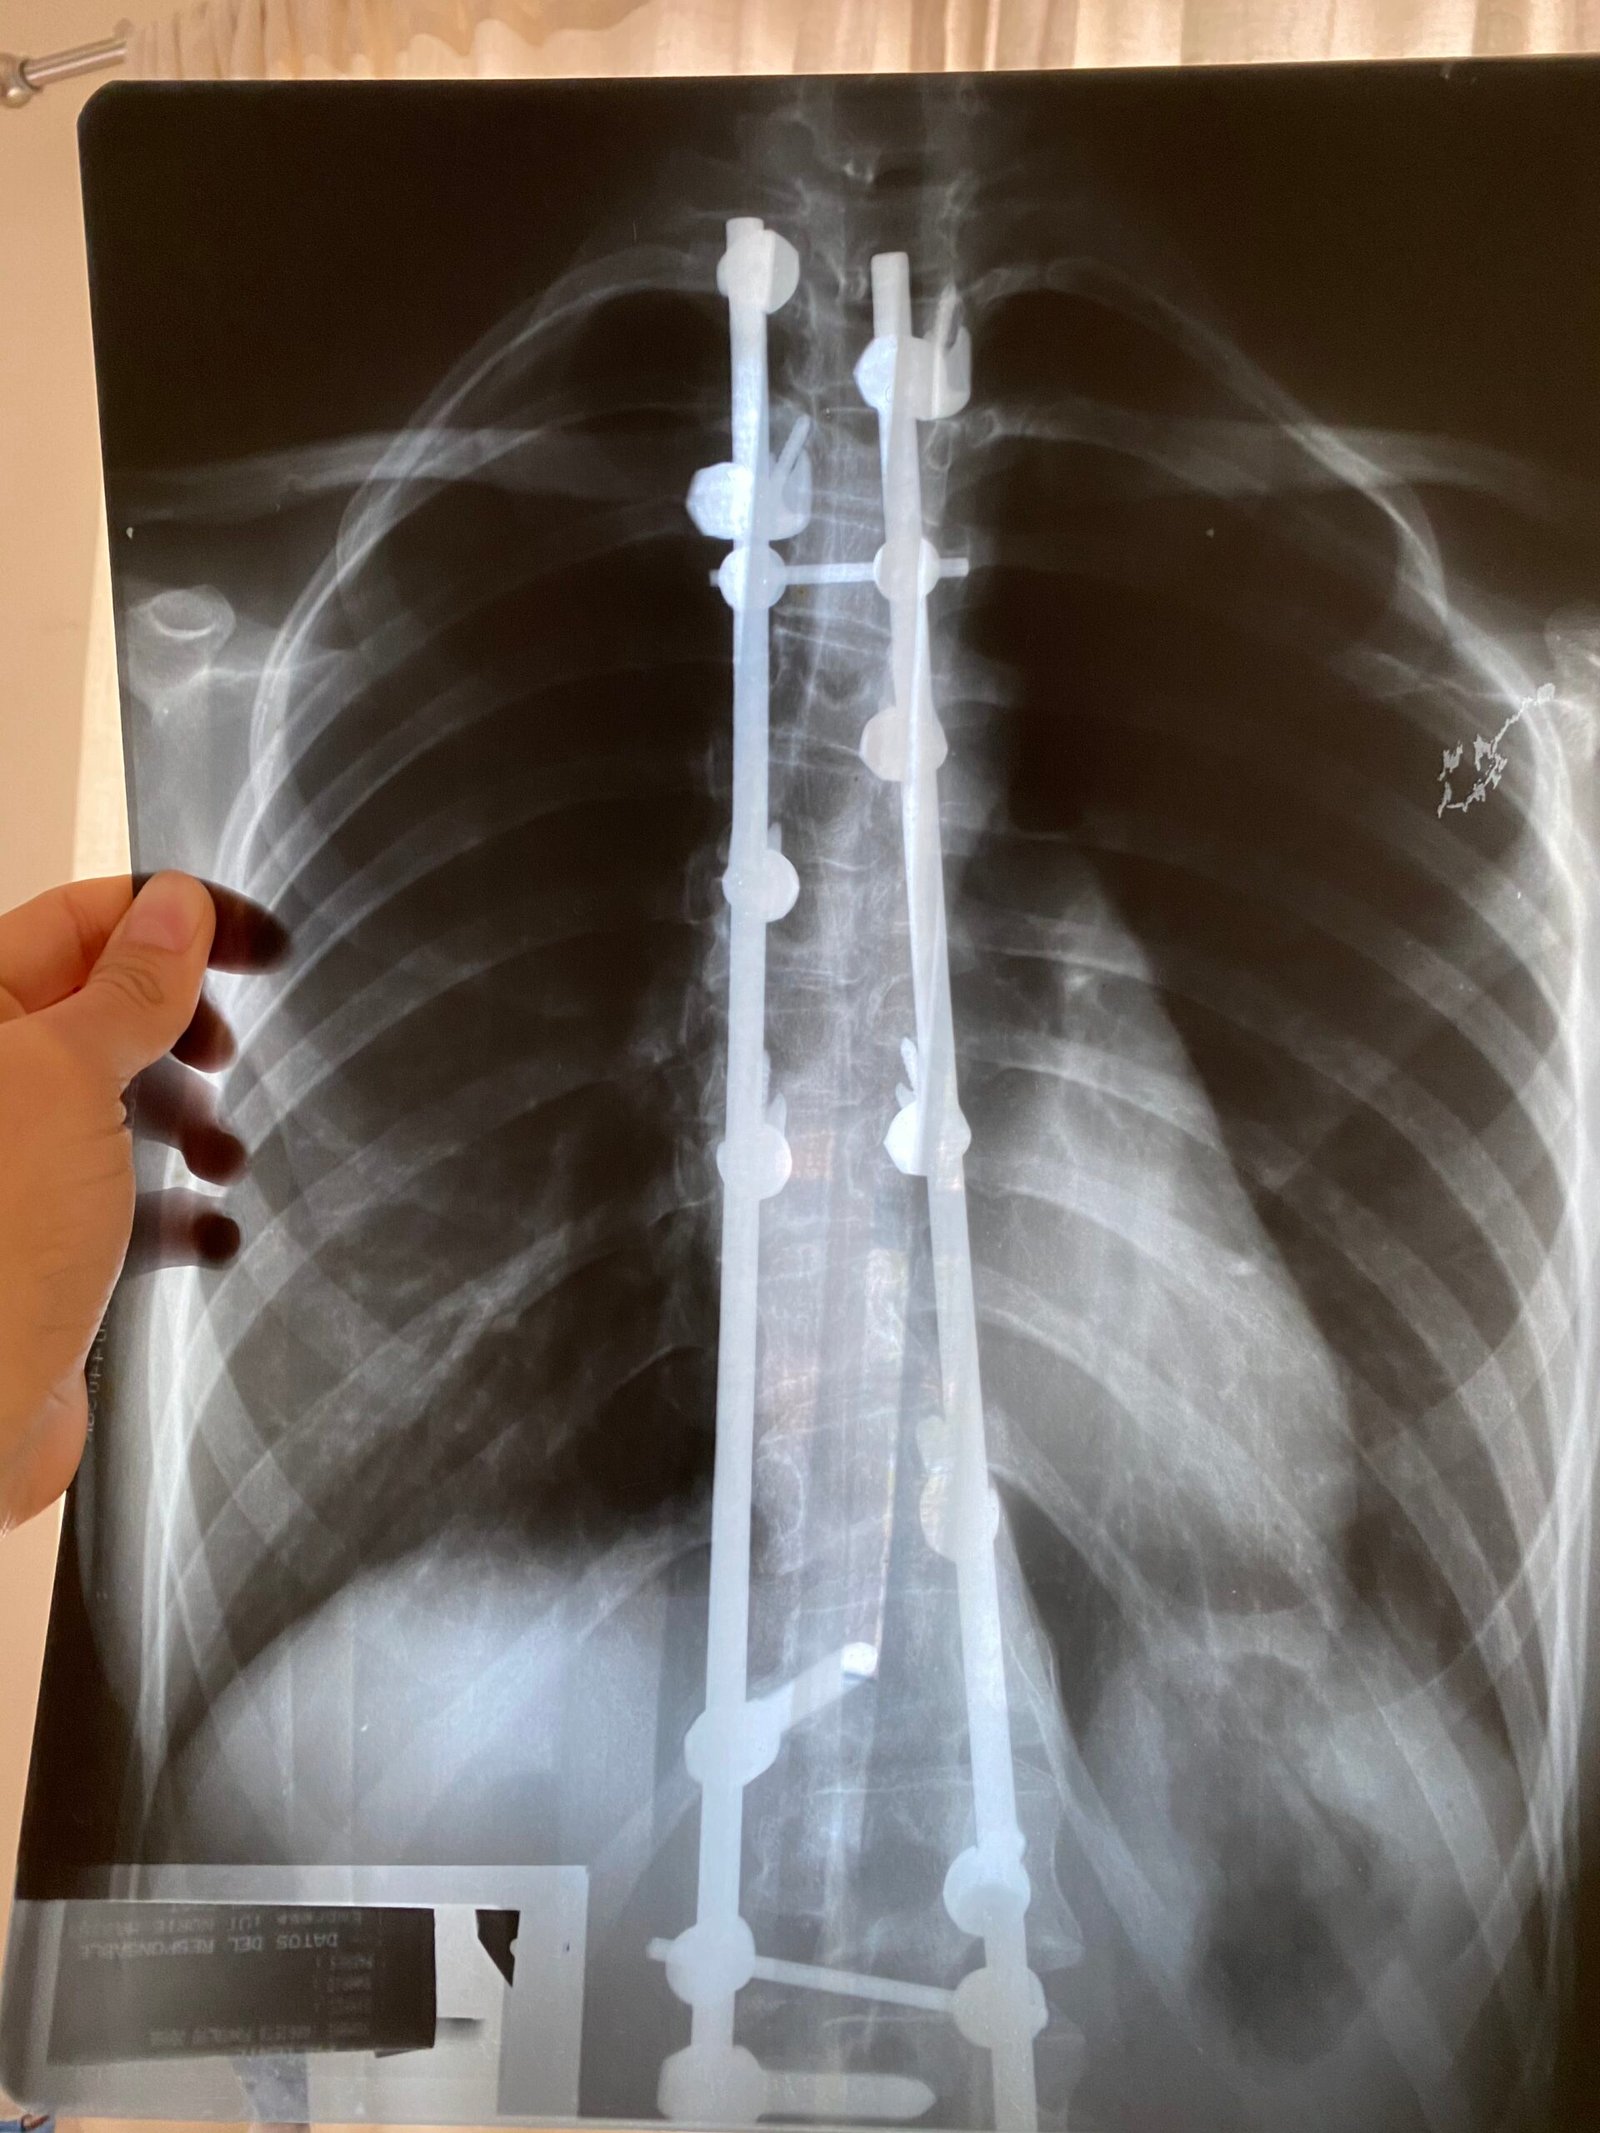

Cuando tenía 15 años y me dijeron que mi columna jamás volvería a ser la misma, sentí que mis sueños se apagaban. Cuando me dijeron que no podría tener un parto natural, sentí miedo y dudas. Y cuando la vida me puso frente a dolores físicos, emocionales y espirituales, más de una vez pensé que no iba a poder.

Conozco a Joyce Sierra a través de sus redes, y aunque aún no hemos coincidido en persona, su ejemplo ha transformado mi vida. Tengo 25 años y convivo con escoliosis, una condición que a veces trae dudas y miedos. Ver a Joyce enfrentar sus retos con valentía, disciplina y constancia me enseñó que muchas barreras están en la mente y que con determinación los sueños sí se pueden alcanzar.